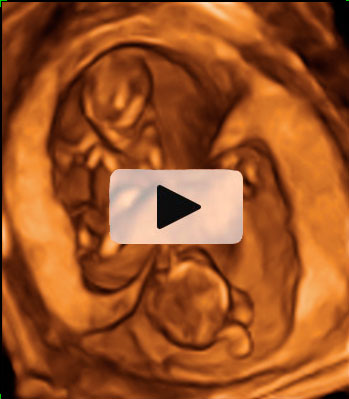

Ecografía 2D y 3D de la semana 12: embarazo de trillizos

Vemos tres planos de un embarazo de trillizos en ecografía 2D en diferentes cortes de imagen. Lo que vemos en 3D es lo que los ecografistas conocen como "un queso", es decir el embarazo visto en tres dimensiones desde una perspectiva determinada. Lo que realmente esconde ese peculiar queso es un embarazo de trillizos: un feto independiente, separado de sus hermanos por una membrana.

Los gemelos se desarrollan en dos bolsas diferentes. En otro corte de la imagen, se ve un embrión independiente separado por una membrana de los otros dos hermanos, que se sitúan en bolsas independientes.